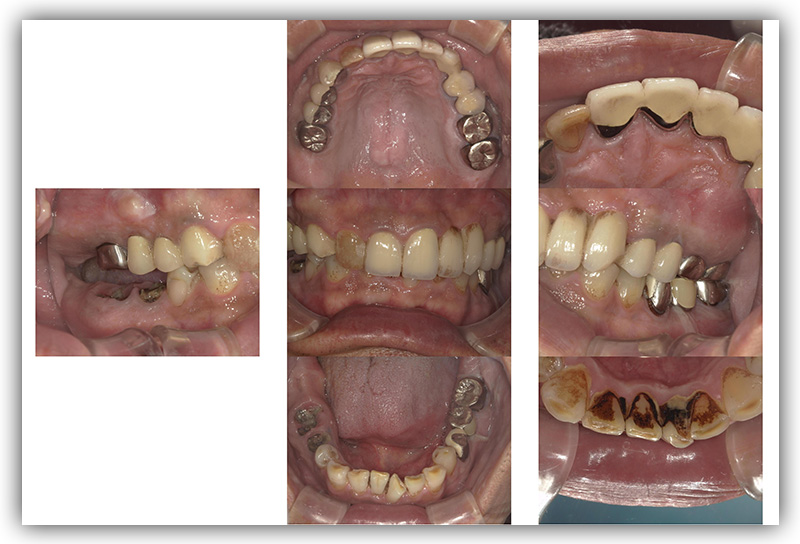

CASE_04

60代女性(インプラント)

- 60代 女性

- 左下のインプラントを考えているが、怖い

- インプラント1箇所、セラミック3箇所

- インプラント、セラミック治療

- インプラント42.9万円、セラミック治療約24万円

- 約1年6か月

- 保険が効かない

- 外科的治療が必要